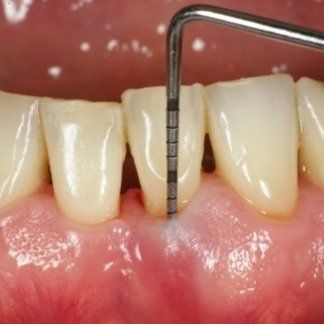

It is based on a very simple tool: the millimetreed periodontal probe applied with slight pressure inside the periodontal pocket.

- The probing depth and, consequently, the changes in the amount of periodontal attachment: An increase in probing depth over time is synonymous with a loss of tooth support structures.